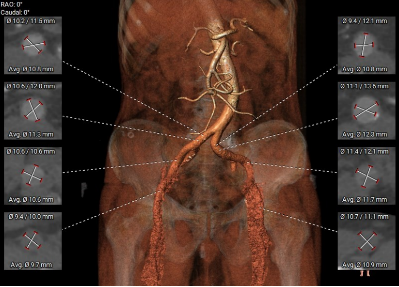

血管三维重建